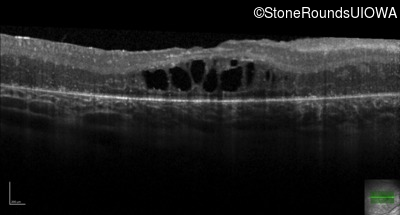

Age at visit: 17 years

This 17 year old female feels that the vision in her right eye has worsened since her cataract surgery 8 weeks ago.

SECORD CRB1 Cys195Phe TGC>TTC Gly750Asp GGC>GAC AR